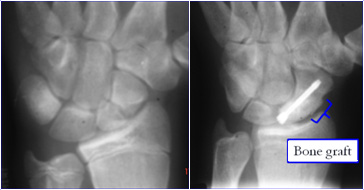

Surgery to treat a non union uses bone graft which may be taken from the hip or the radius.  The bone used in grafting has lots of bone healing cells in it, when placed in the fracture site it helps the non-union to heal.  When taken from the hip only a 1cm chunk of bone is removed, however the operation site is reported as being very painful for a few weeks.  The wound and dressings should be treated in the same way as the wrist wound (see below).   The non union site is cleaned back to healthy bleeding bone.  The bone graft is then packed into the gap and held with a headless screw.

This is the term given to bone which has died because it has not got a blood supply; typically affecting non union of a proximal pole fracture.   The bone may look white on an x-ray or show up as dark on an MRI scan.  Because the bone is dead it had 'turned to chalk' and is very difficult to get to heal.  In this instance a vascularised bone graft may be used.  This involves taking a piece of bone from the radius that unlike the bone graft used normally, has a small blood vessel feeding it.  Next the small square of bone with the vessel and placing it is lifted into the non union site.  In this way the blood supply is plumbed directly into the dead bone.  Even with this advanced surgery the success rate of gaining a healthy united scaphoid in the presence of AVN is only 40-55%.